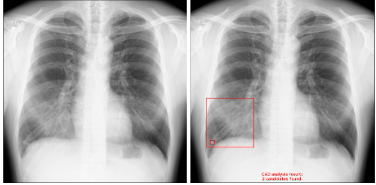

【画像例】

・浸潤影の内側に結節影がある症例

・右肺に無気肺がある症例

・間質性陰影が広がっている症例